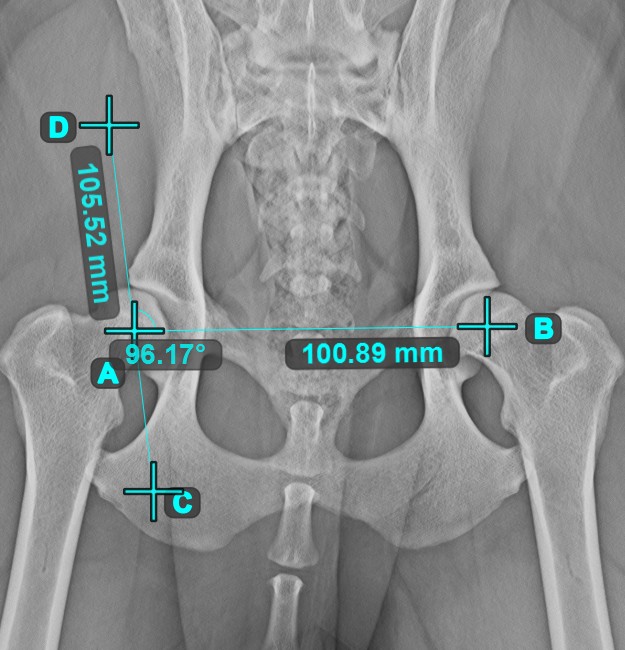

Winkel zwischen Linien¶

Berechnen Sie den Winkel zwischen zwei unabhängigen oder sich schneidenden Linien mit dem Werkzeug Winkel zwischen Linien

.

Wählen Sie das Werkzeug aus der linken Symbolleiste aus und weisen Sie es einer der verfügbaren Maustasten zu. Beginnen Sie, indem Sie die erste Linie aus den bereits in der Szene gezeichneten Linien auswählen oder Start- und Endpunkt setzen, um die Linie zu erstellen. Wiederholen Sie die gleichen Schritte für die zweite Linie der Messung. Der Winkel zwischen den beiden Linien wird automatisch berechnet.

Ändern Sie die Start- und Endpunkte beider Linien mit dem Werkzeug Objekt auswählen/verschieben

. Der Winkel zwischen den beiden Linien wird automatisch neu berechnet.

Informationen

Wenn sich zwei Linien nicht direkt schneiden, wird der Winkel ihrer verlängerten Projektionen in der Szene berechnet.